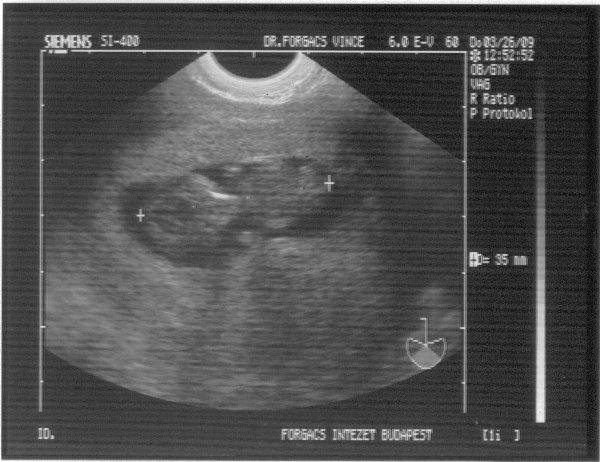

A baba miatt meg ne aggódj! Hidd el, nem lesz semmi baj. Azért a nemét megmutathatta volna. Már olyan kivi vagyok.

És még szebb a babád! Annyira jó érzés lehet ezeket a képeket nézegetni.